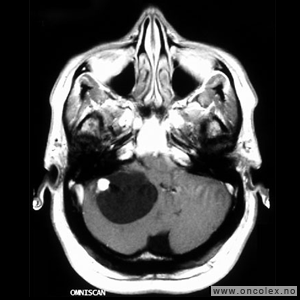

Knosp klassifikasjon brukes for å beskrive svulstenes utbredelse fra midtlinjen og ut til sidene. Klassifikasjonen deler svulstene inn i grad fra 0 til 4, hvor grad 0 er svulster i hypofysegropen uten utbredelse inn i sinus cavernosus, og grad 4 er svulster som omslutter den indre halsarterien (arteria carotis interna). Grad 4 svulster og svulster som brer seg ut til siden for den indre halsarterien (Knosp grad 3) er svært vanskelig å fjerne fullstendig med operasjon.

Bildeserie av stadieinndeling av hypofysesvulster (Knosp klassifikasjon)